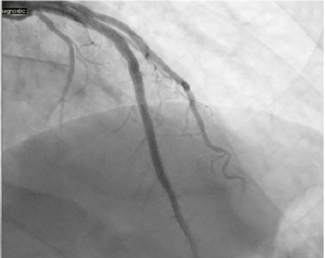

A 56-year-old male with a past medical history of gastroesophageal reflux disease and tobacco abuse presented to the emergency department with a chief complaint of chest pain and progressive shortness of breath of a year duration. The patient...